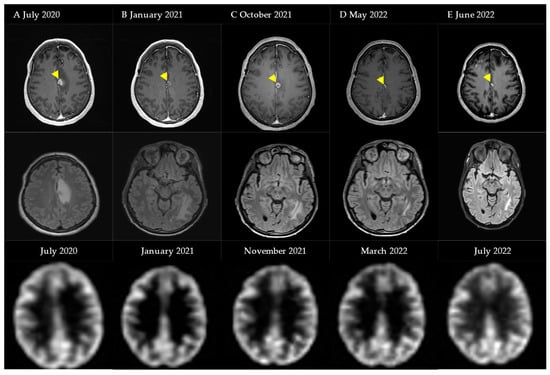

4.1. Case Illustration 1

4.2. Case Illustration 2